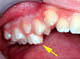

Doppelte Zahnreihe? Nicht ganz. Aber dieser Milchzahn (Pfeil) will einfach nicht herausfallen und behindert den bleibenden Zahn beim Durchbruch.